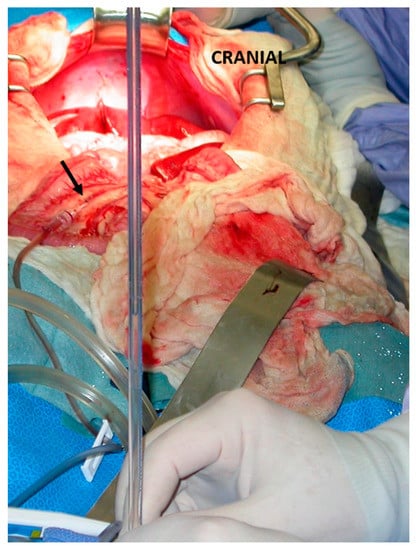

3.1. Suture Ligation